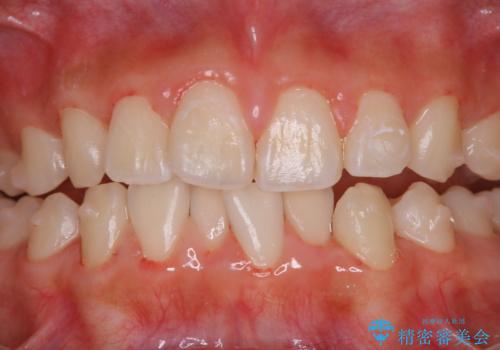

PMTC30分コースを行いました。

矯正治療中も清潔な口腔内を保つことは、とても大切です。そのため、定期的に専門的な機械・材料を使用したProfessinnalcleaning(pmtc)を行うことがおススメです。